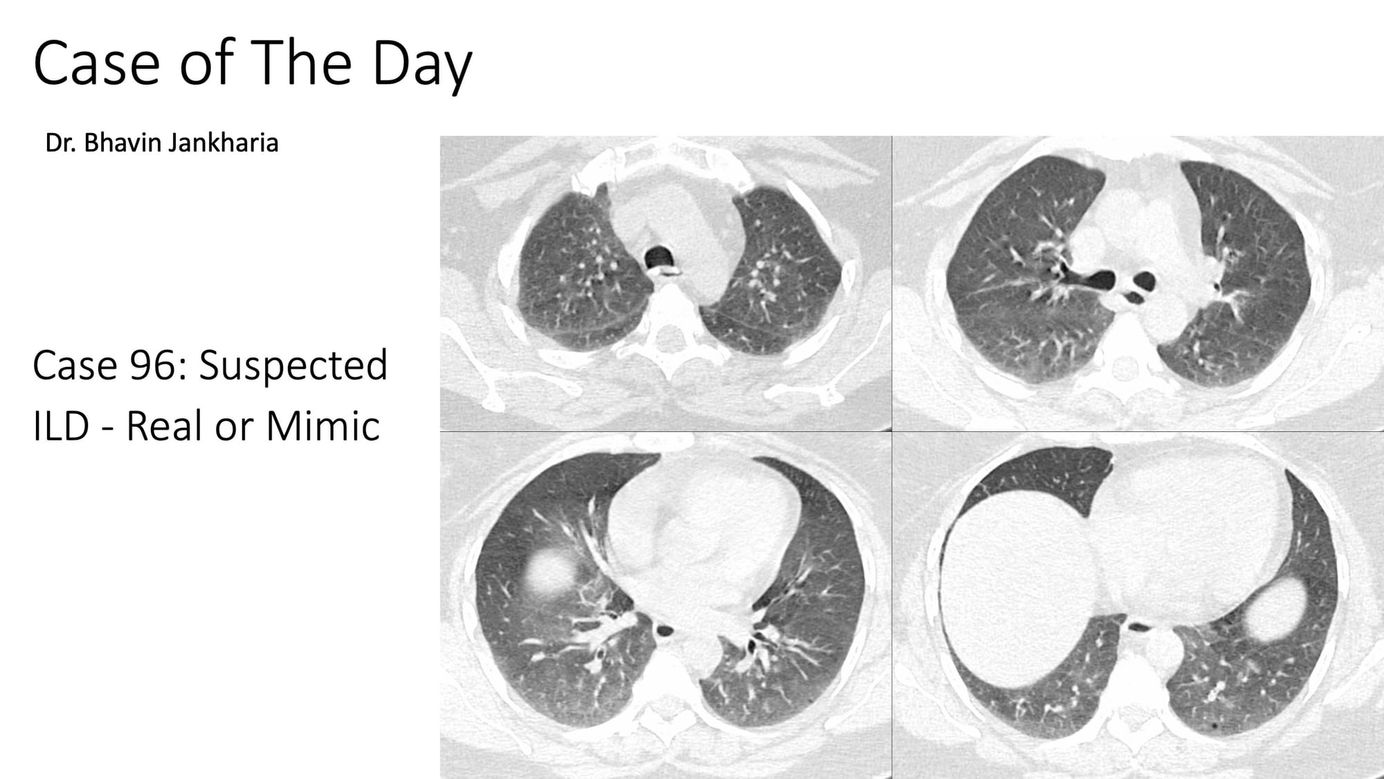

Case of the Day 096 - Suspected ILD - Real or Mimic? Paid Members Public

A poor quality scan (blurred, expiratory) can be misdiagnosed to have disease with adverse consequences.